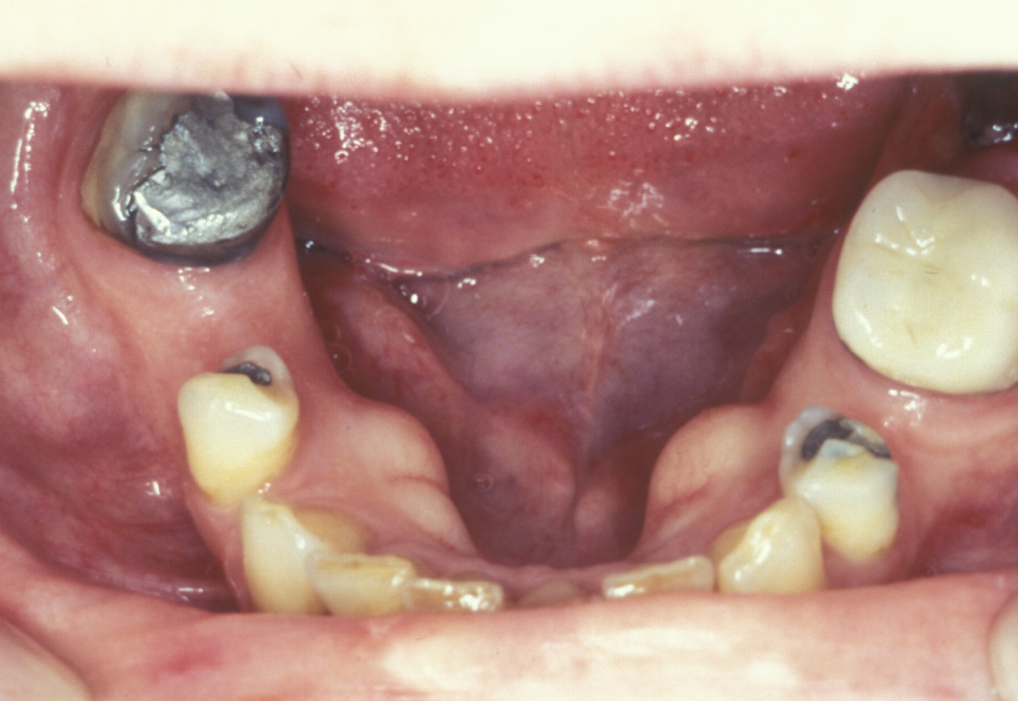

A torus is a bony exostosis (outgrowth) of the jaw. Torus palatinus occurs in the centre of the hard palate (see Figure 9), torus mandibularis occurs in the lingual (tongue-side) premolar or molar region of the mandible (see Figure 10). These lesions are entirely benign and only require removal when they are symptomatic or for reasons of prosthetic functionality.

Figure 9: The appearance of torus palatinus.

Figure 10: The appearance of torus mandibularis.